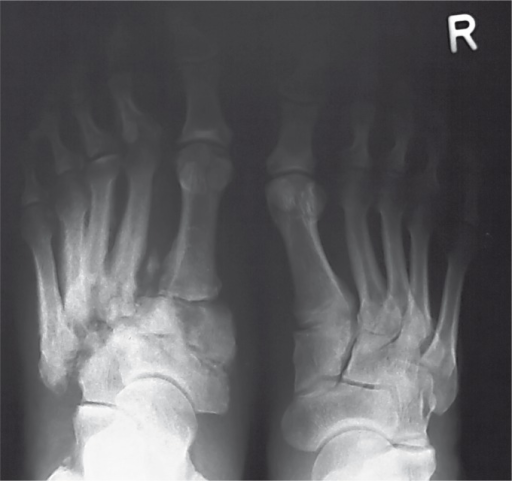

Clinical image for Charcot Neuroarthropathy

Describe your assessment of this patient. What investigations would you order and how would you interpret them?